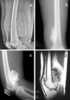

High-grade intramedullary osteosarcoma